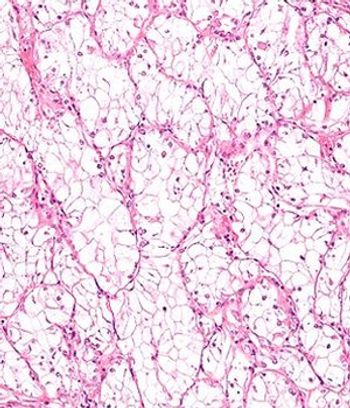

A 16-gene Recurrence Score was found to be significantly predictive of recurrence-free interval and survival in patients with stage I-III clear cell renal cell carcinoma who have undergone nephrectomy.